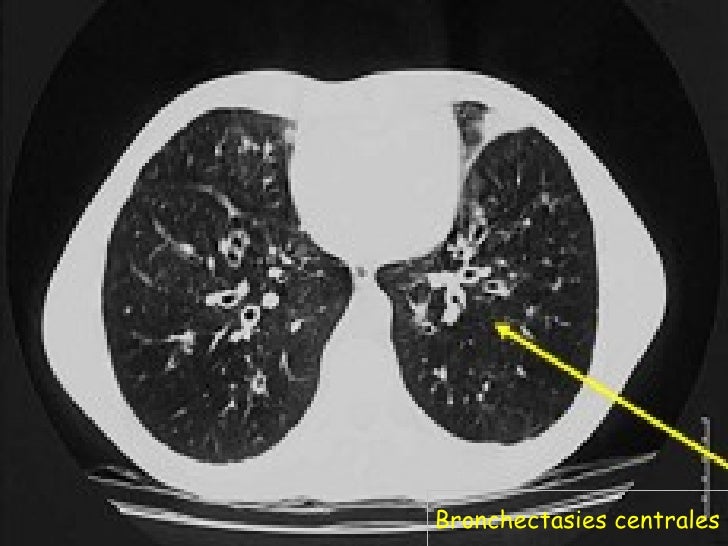

Responsable d'aspergillose bronchopulmonaire allergique (asthme aspergillaire), d'aspergillomes ou d'aspergilloses profondes. Es kann lange zeit unentdeckt bleiben, anfängliche beschwerden können eitrige sekretion, nasenbluten oder ein druckgefühl auf der betroffenen seite sein. Aspergillus fumigatus ist ein schimmelpilz aus der gattung der gießkannenschimmel (aspergillus) in der familie der trichocomaceae.der name stammt von lat. Die infektion betrifft häufig die nasennebenhöhlen und die lunge. Bakterien, die für ihren stoffwechsel sauerstoff brauchen, bezeichnet man als aerobe bakterien oder aerobier. It generally occurs in people with lung diseases such as asthma, cystic fibrosis or tuberculosis, or those who have had a stem cell or organ transplant, and those who cannot fight infection because of m. Aspergillosis is a fungal infection of usually the lungs, caused by the genus aspergillus, a common mold that is breathed in frequently from the air around, but does not usually affect most people. La société de réanimation de langue française (srlf) est heureuse et fière de vous présenter son nouveau site internet.

Die infektion betrifft häufig die nasennebenhöhlen und die lunge. Aspergillosis is a fungal infection of usually the lungs, caused by the genus aspergillus, a common mold that is breathed in frequently from the air around, but does not usually affect most people. Typischerweise wird nur eine seite befallen. Bakterien, die für ihren stoffwechsel sauerstoff brauchen, bezeichnet man als aerobe bakterien oder aerobier. La société de réanimation de langue française (srlf) est heureuse et fière de vous présenter son nouveau site internet. Aerob bedeutet sauerstoffabhängig oder sauerstoff verbrauchend. It generally occurs in people with lung diseases such as asthma, cystic fibrosis or tuberculosis, or those who have had a stem cell or organ transplant, and those who cannot fight infection because of m. Responsable d'aspergillose bronchopulmonaire allergique (asthme aspergillaire), d'aspergillomes ou d'aspergilloses profondes. Aspergillus fumigatus ist ein schimmelpilz aus der gattung der gießkannenschimmel (aspergillus) in der familie der trichocomaceae.der name stammt von lat. Ze zitten op de huid, maar komen ook in het lichaam voor. Fumus, der rauch und entstammt der rauchgrünen farbe des pilzes, die von einem pigment in den sporen verursacht wird. Die allergische form einer erkrankung durch aspergillen ist die allergische bronchopulmonale aspergillose. Bei der invasiven aspergillose, die bei immunschwäche auftritt (z.b.